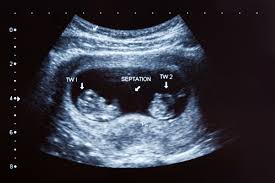

An ultrasound scan is the only way to confirm that you re pregnant with twins mcaslan fraser nd nice 2011. After week 6 0 both hearts should be beating. As the babies grow there tends to be more movement and light flutters felt in the abdomen by the pregnant woman. Regardless elevated beta hcg levels in early pregnancy isn t a proper way to detect twins.

The earliest you re likely to find out is between 10 weeks and 14 weeks when you have your dating scan mcaslan fraser nd nhs 2019 nice 2011. If they are mo di or mo mo twins you have to wait until 6 full weeks have passed. All fraternal twins and 20 to 30 percent of identical twins have separate placentas. Generally when you are pregnant with twins fetal movements become more noticeable at weeks 18 through 20 of pregnancy and the same is true in singleton pregnancies al khan says.